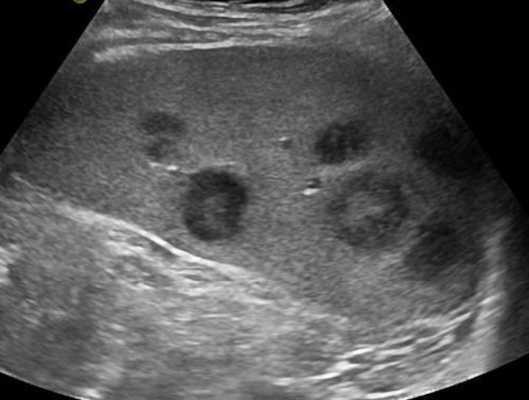

- Лучший диагностический ключ. Нормальный или слегка увеличенный лимфоузел в известном анатомическом положении. Другие реактивные узлы на шее, односторонние или двусторонние. Несколько хорошо очерченных, овальных узлов

- Морфология. Узел обычно овальный, а не круглый

- Гипоэхогенная кора по сравнению с соседней мышцей ± кортикальная гипертрофия

- Обычно овальной формы, за исключением подчелюстных узлов, которые обычно округлые

- Увеличенный лимфоузел, сохранилась хиларская архитектура. рубчик; интранодальный, линейный, эхогенный и непрерывный с границей с мягкими тканями вокруг лимфатического узла. Хиларная эхогенность обусловлена наличием множества звукоотражающих поверхностей от афферентных и эфферентных лимфатических узлов, артерий и вен, расположенных в пределах шеи и грудины.

- Отсутствие интранодального некроза или узлового матирования

- Соседние мягкие ткани явно не воспалены. Нет признаков сопутствующего целлюлита или абсцесса